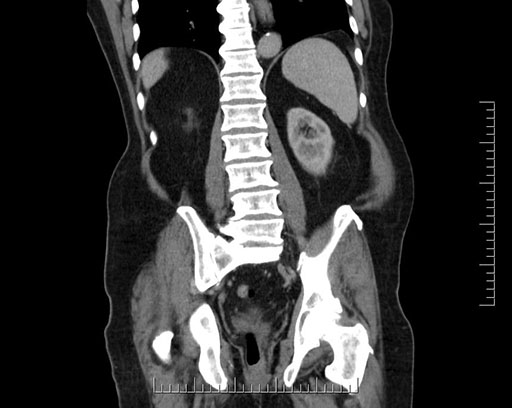

Whipple (pancreaticoduodenectomy) [case 7]

Imaging Analysis

Look through the patient's CT scan to identify any areas of concern for the necessary procedure.

Based on your CT findings, which issue(s) would give reason for "planned slowing down moment(s)" in this case?

Considering a standard Whipple procedure, what step(s) of the operation would you do differently in this case?